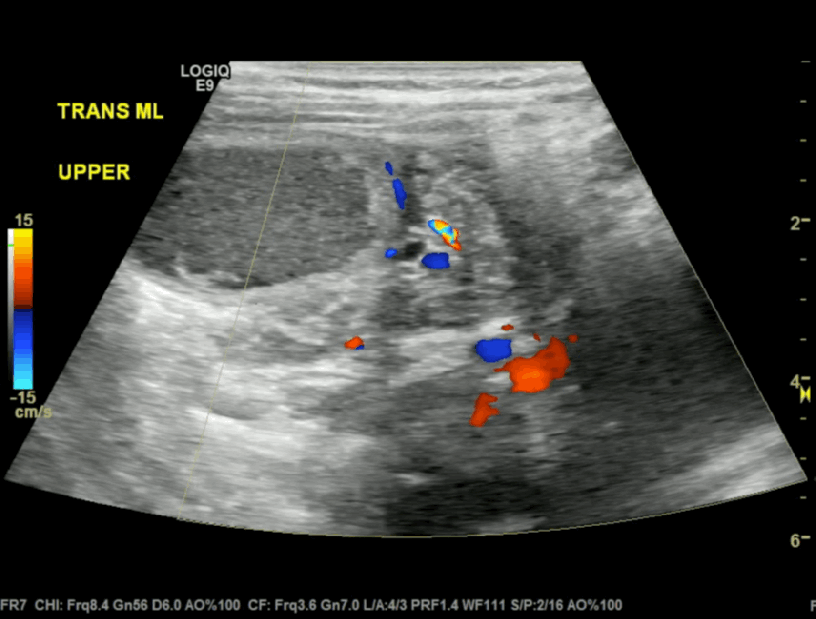

Paediatric Abdominal POCUS Emergencies